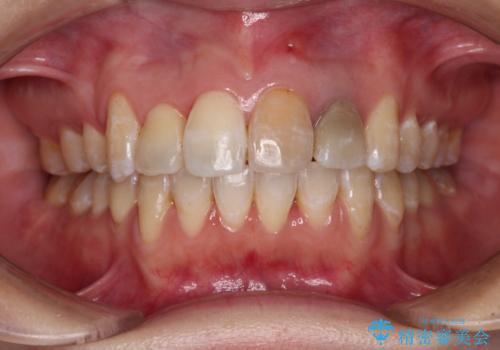

ワイヤー矯正を併用し、リスクを回避しながらのインビザライン矯正治療